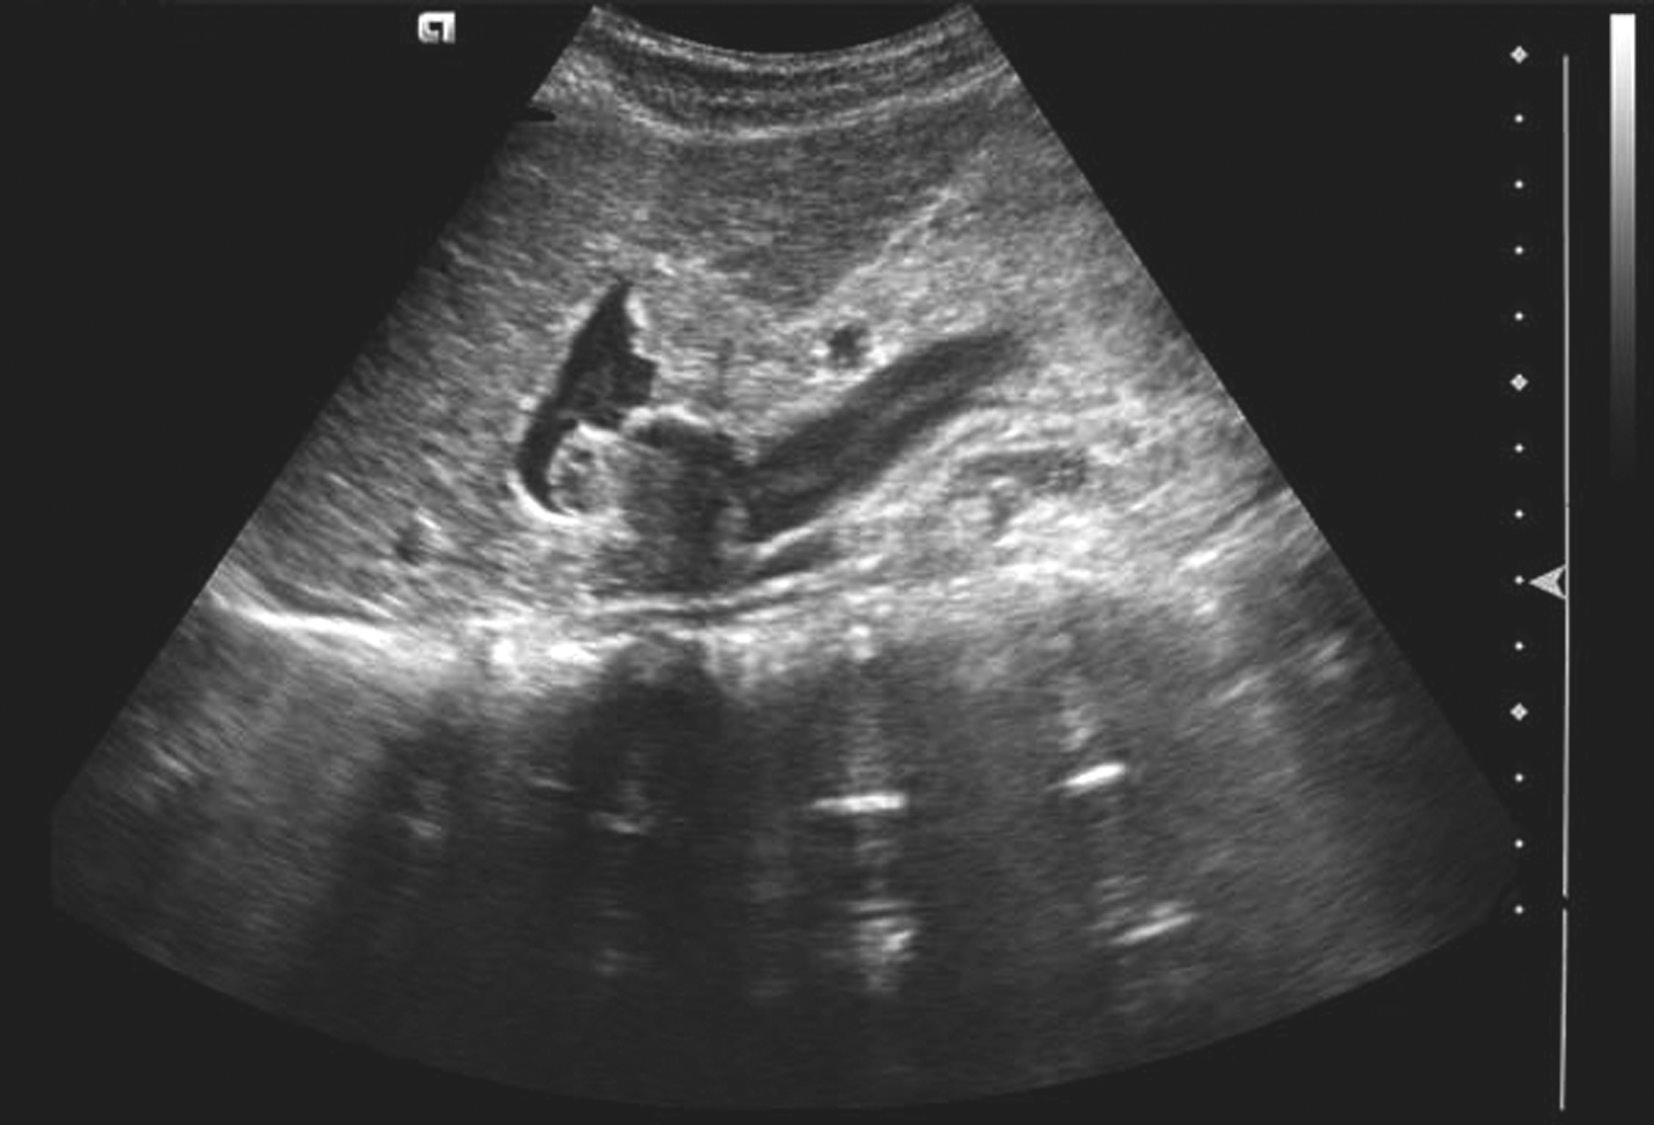

肝内管道结构的超声测量如图5-21-1~图5-21-3所示:

图5-21-1 肝右叶前后径测量切面

图5-21-2 肝右叶最大斜径测量切面

图5-21-3 肝左叶前后径和上下径测量切面